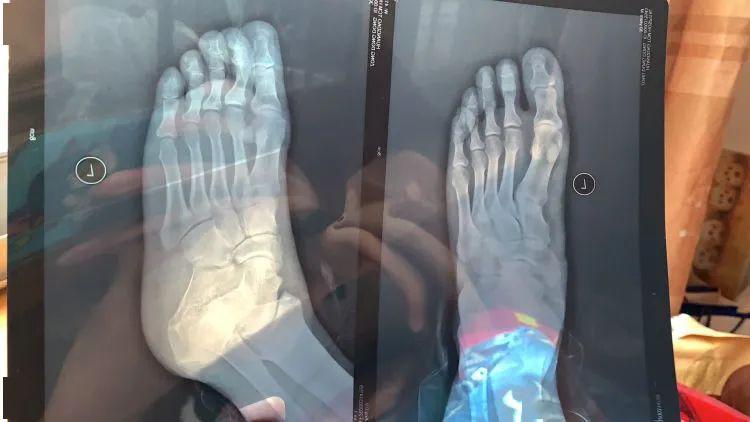

宗先生介绍,他当时在大门处站着,这位售后人员将车辆停下后询问他车辆有什么问题,何处漏油,并示意宗先生上前指给他看,随后,这位售后人员将车辆降落时,升降机压到宗先生的脚趾上。“当时脚流了不少血,我赶紧到医院检查。”宗先生说道。半岛全媒体记者从医院的诊断报告上看到,宗先生 “左足踇趾末节趾骨骨折”。

医院检查结果显示其骨折。